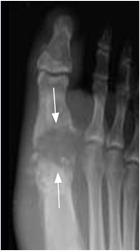

Fig 64 B . Artritis séptica.

Rx AP. Artritis infecciosa del pulgar, con zonas de osteolisis en la base de la falange y la cabeza del metatarsiano. (Flechas). Hay edema asociado de los tejidos blandos.